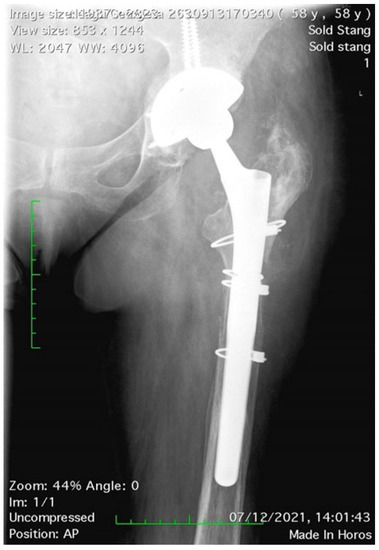

The length of the osteotomized bone fragment (OBF) is essential; it must be long enough to allow the easy removal of the stem with or without cement but without affecting the primary stability of the revision stem. Accurate preoperative planning is very important for this reason. On the right magnification A-P and profile hip X-rays, we measured the length of the stem and the length of the distal cement plug including the length of the plastic restrictor, taking the tip of the greater trochanter as a reference point. For cementless stems, it is not necessary for the OBF to reach the level of the stem tip, only up to approximately 2 cm, whenever it is preoperatively intact (Figure 1). Maintaining the integrity of at least the femoral isthmus is mandatory. Usually, the length of the OBF is 15–16 cm. A varus remodeling aspect can be corrected by adding the osteotomy of the internal cortex (Figure 2).

In 30% of stem loosening cases, varus remodeling of the metaphyseal–diaphyseal area of the femur has been observed [9]. In these cases, the transtrochanteric approach is associated with an osteotomy of the medial cortex to correct the varus deformity, thus avoiding the perforation or the fracture of the femur while preparing the medullary canal and inserting the stem. In our study, four cases presented with significant remodeling in varus that required osteotomy of the internal cortex; in all cases, we obtained correction of the diaphyseal axis and consolidation of the osteotomy [25].

Figure 2. Internal cortex osteotomy for varus remodeling of proximal femur.